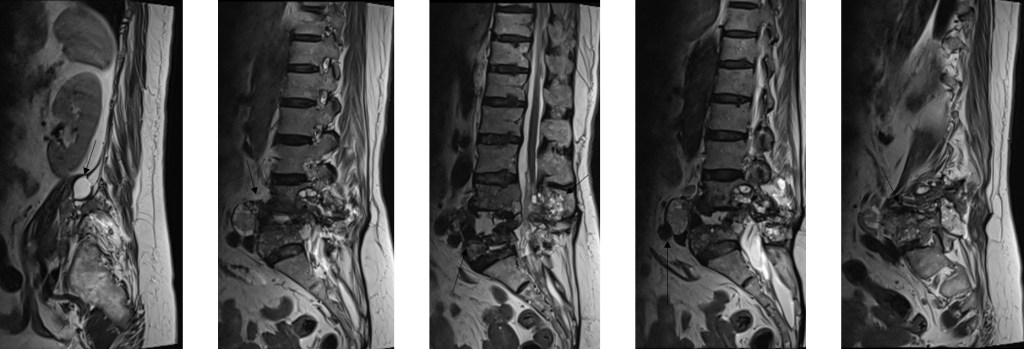

1. Figura 1: Imagini din achiziţia sagital T2 la o pacientă cunoscută cu leziuni vertebrale lombare prin infectie parazitară cu Echinococcus multilocularis. Se observă modificări multichistice ce afectează corpii vertebrali L4 si L5 cu distrucţie osoasă şi se dezvoltă şi la nivelul găurilor de conjugare precum şi în ţesuturile moi de vecinătate.